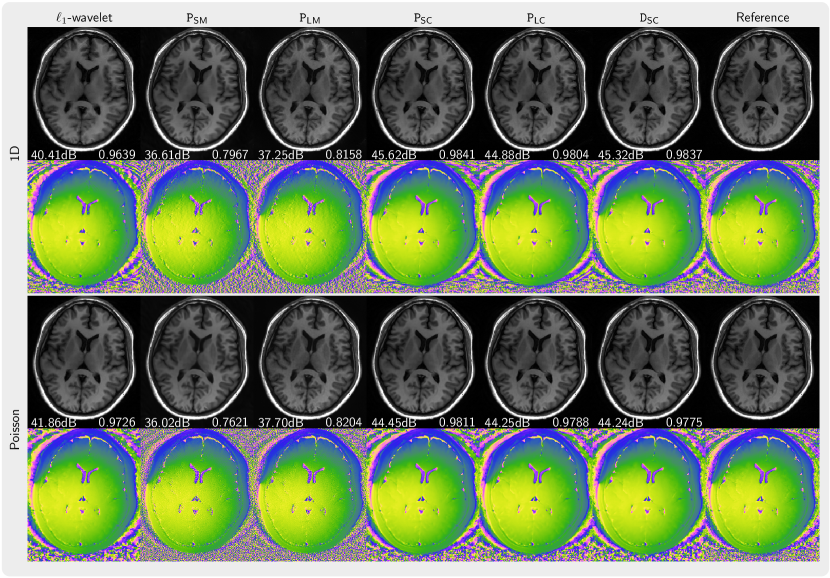

Figure 3 presents the magnitude and phase of images that are reconstructed using PICS with priors trained from magnitude image, complex images with preserved phase, and complex images with generated using our phase augmentation method While the priors PSM and PLM trained from magnitude images can remove folding artifacts introduced by undersampling, they exhibit over-smoothing of the magnitude as indicated by its lower PSNR and SSIM values and also demonstrates poor capabilities in denoising the phase. In contrast, the prior PSC trained on complex-valued images performs much better. Furthermore, the priors PLC and DSC trained on phase-augmented images and perform almost as well. Very similar results were obtained for NLINV as shown in Figure 4. In Figure 5, the k-space is sampled using 2 3 pattern. We observed artifacts (red arrow) introduced by the priors trained from magnitude-only images reconstructed with PICS method, but not with NLINV method. Under all investigated conditions, the priors trained on complex-valued images outperform the reconstruction with -wavelet regularization.